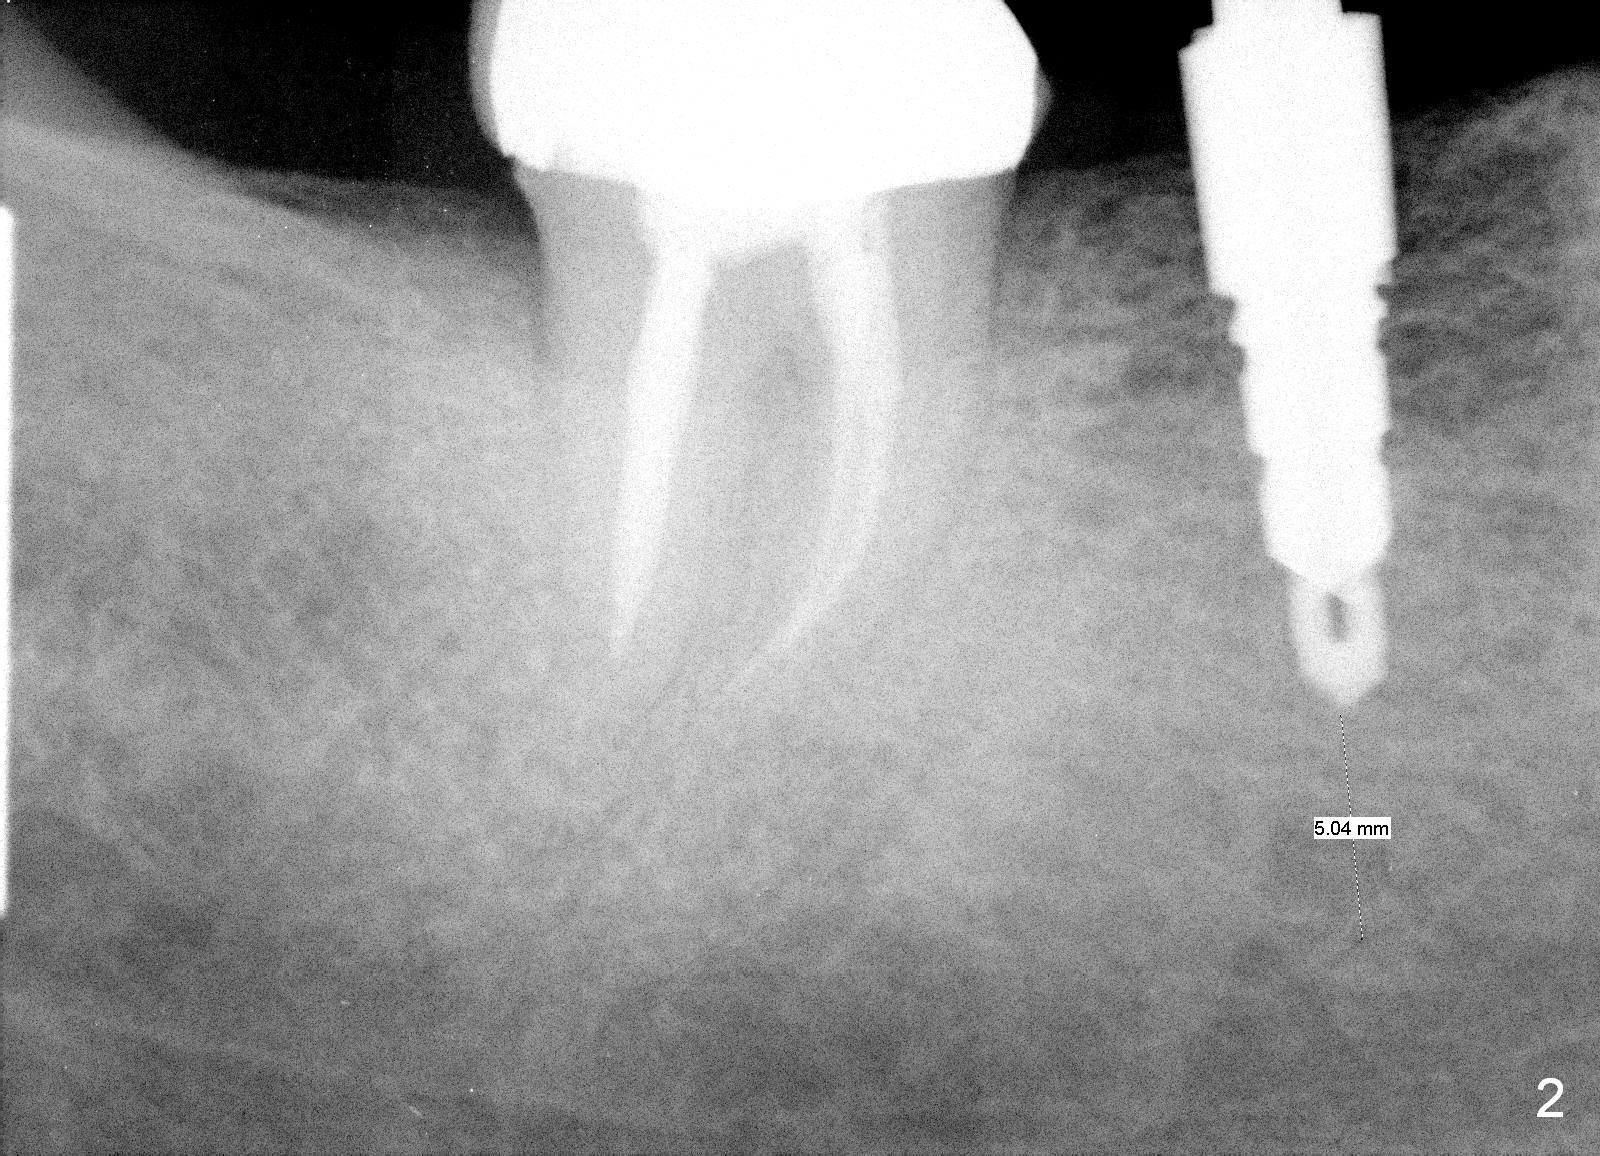

A 47-year-old man has history of bruxism, chipping porcelain from #29-31 FPD (Fig.1). Following sectioning the FPD, osteotomy is created (Fig.2: 5x14 mm drill) for placement of a 5x14 mm tissue-level implant (Fig.3,4). A 4x3 mm abutment (Fig.5 (lingual view) A) with 3 vertical slots (* for increased retention) is placed to retain periodontal dressing. The crown over the implant has dislodged 3 times over 28 months post cementation (Fig.6). It appears that the top of the abutment is too rounded. Clinical exam shows that the abutment height can be more, although the tooth #3 is supraerupted (Fig.7 (orthodontic intrusion is not indicated because of furca infection)).

Pre-impression photos show supraerupted #3 (Fig.7). Clearance is a little more than 1 mm between the mesiopalatal cusp of #3 (Fig.7 *) and the rounded abutment (Fig.8). Removal of the abutment turns out to be easy. Reduction is confined to the opposing tooth (slopes of the cusps). No occlusal reduction is done for the new abutment as mentioned above except for 2 retention grooves. One-mm reduction ring barely passes the occlusal clearance (Fig.9). No cement is applied to the abutment in case a longer abutment may be required. Bone density seems to remain the same or increase after cementation of a new crown (Fig.7). The redo crown remains in place 1 year post cementation.